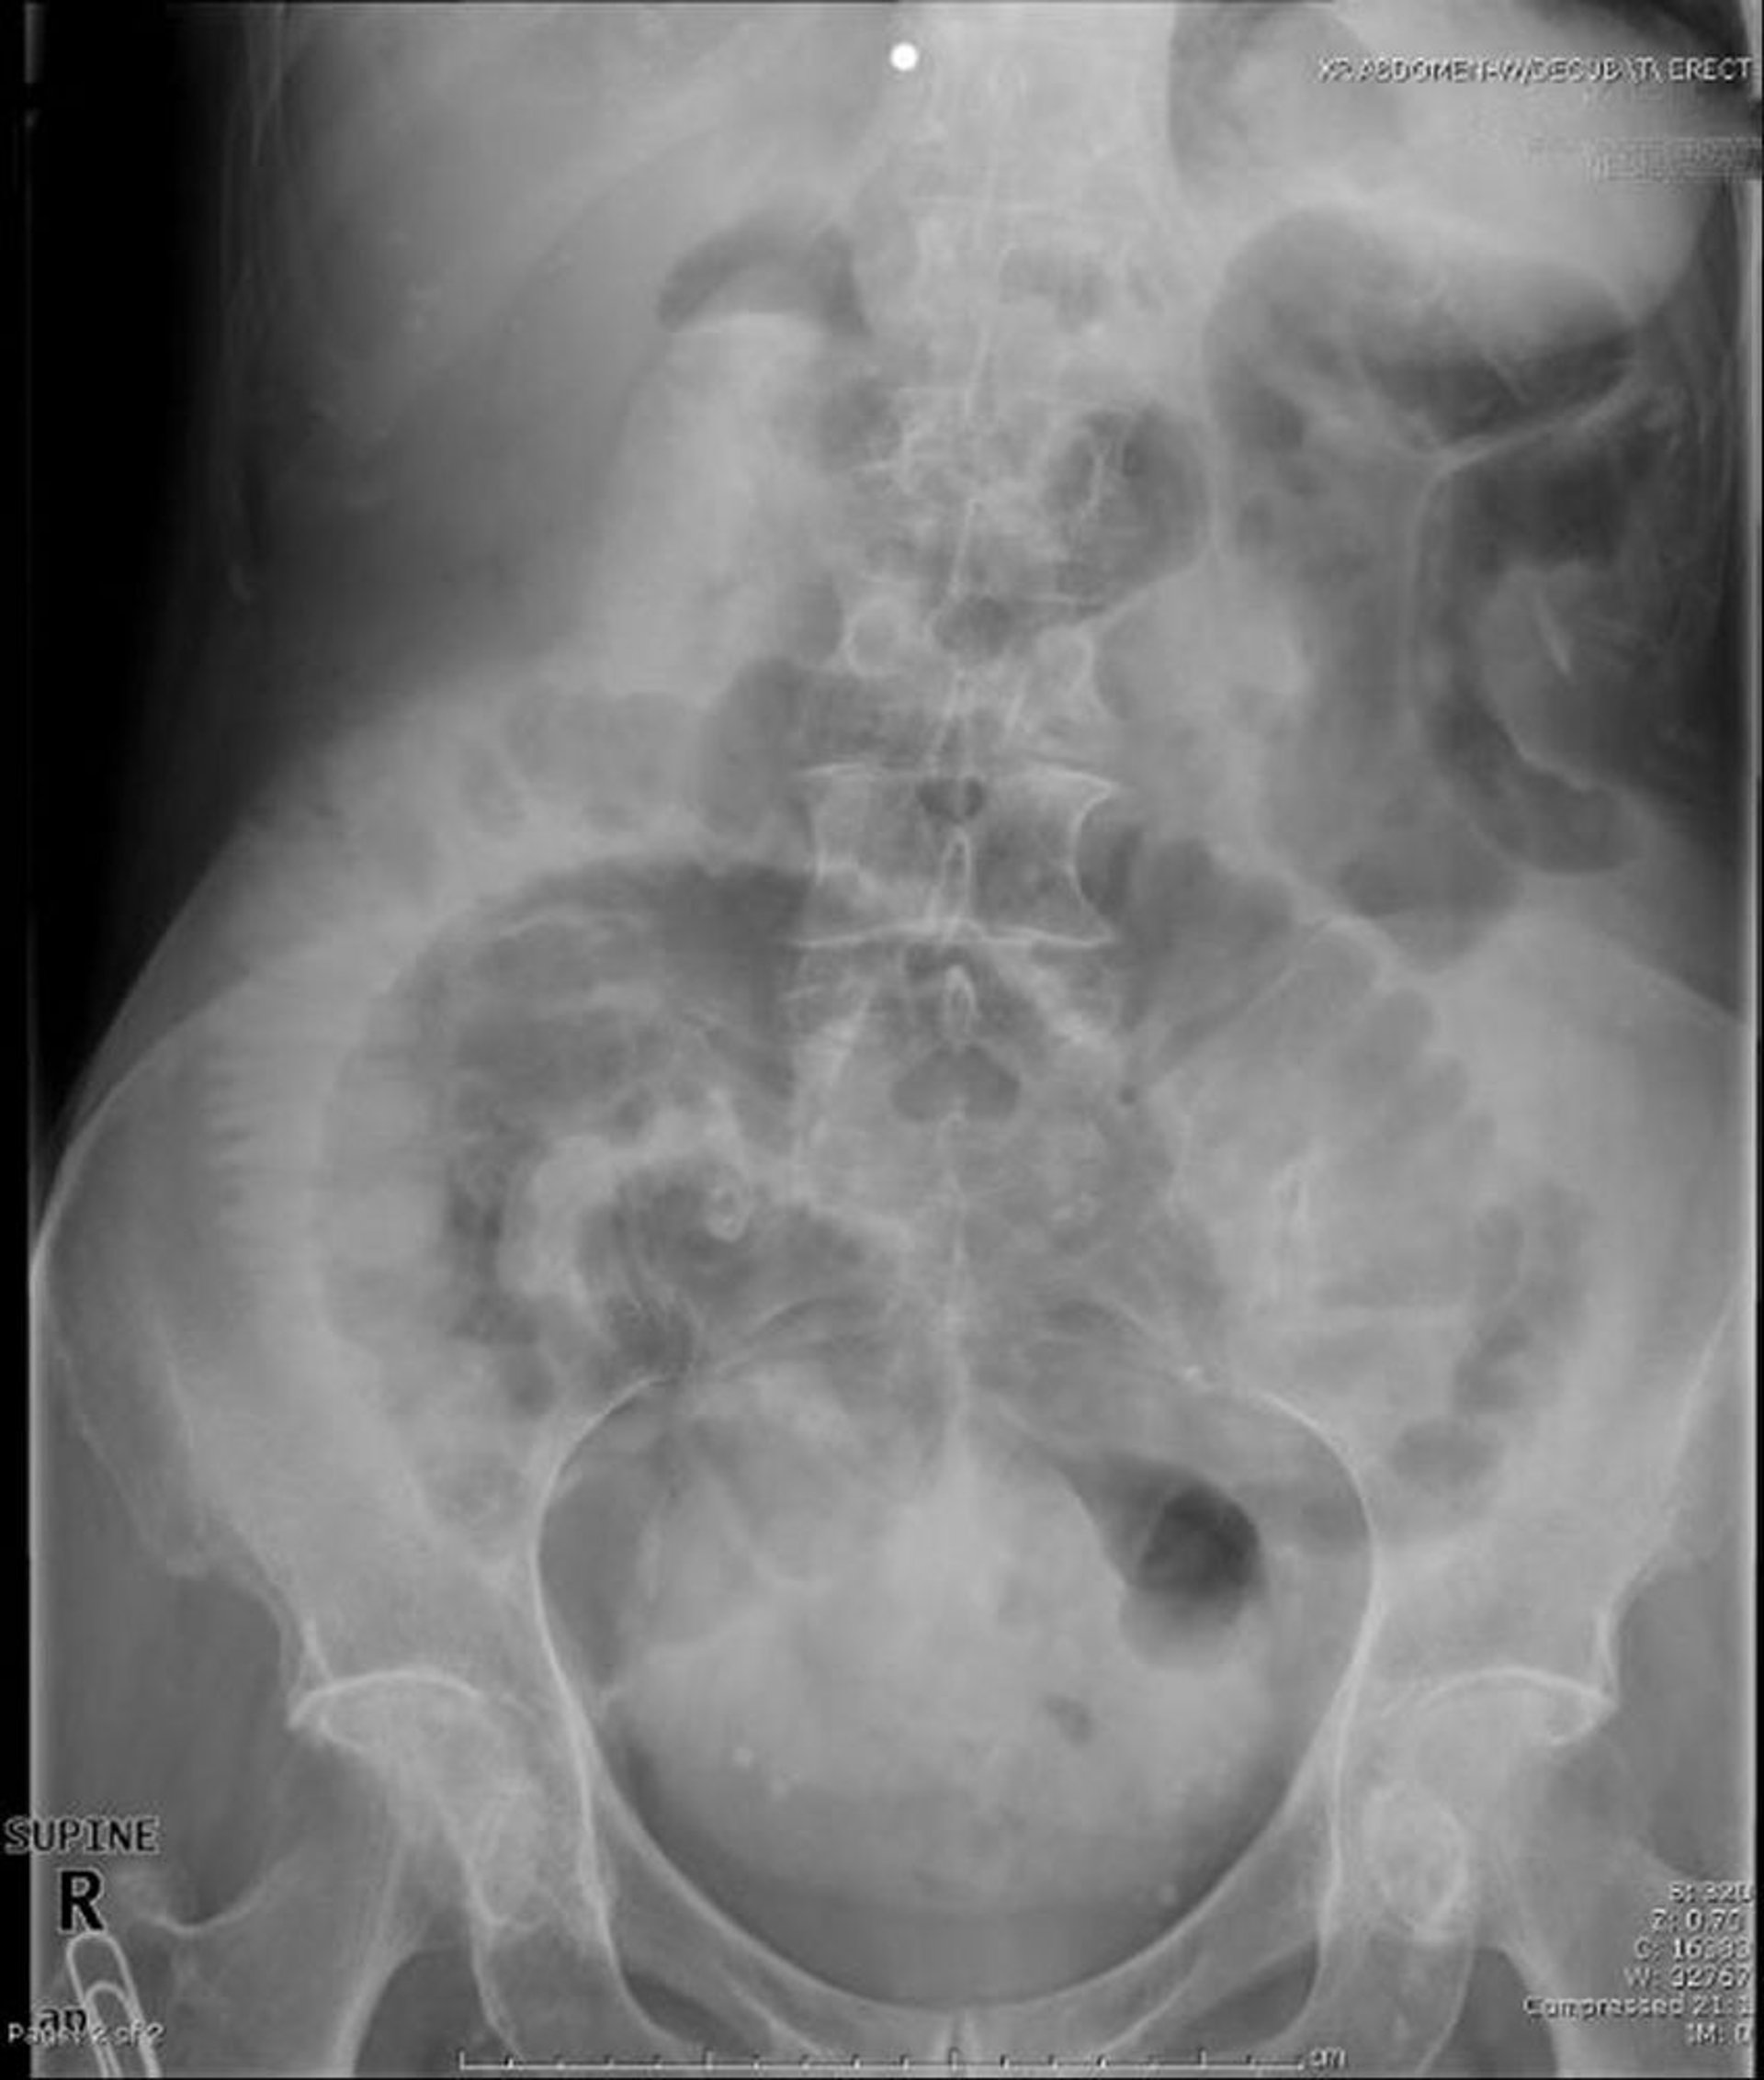

Obstrução do intestino delgado (radiografia supina)

Essa radiografia abdominal supina mostra obstrução do intestino delgado. Observe as alças dilatadas do intestino delgado.

Image provided by Parswa Ansari, MD.